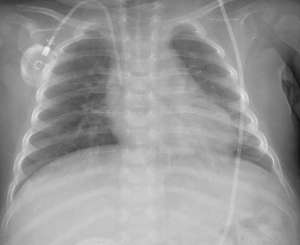

Chest radiography after two months of ruxolitinib therapy showed sufficient improvement for weaning off of mechanical ventilation.

Within two months of ruxolitinib therapy, the boy was well enough to be weaned off of mechanical ventilation and is now, two years into therapy, in full remission of the clinical signs of the disorder. He is receiving follow-up treatment from an outpatient clinic and “continues to grow normally”, albeit “with slower progress in his developmental milestones,” the researchers say. The child will likely need to take ruxolitinib for the rest of his life.